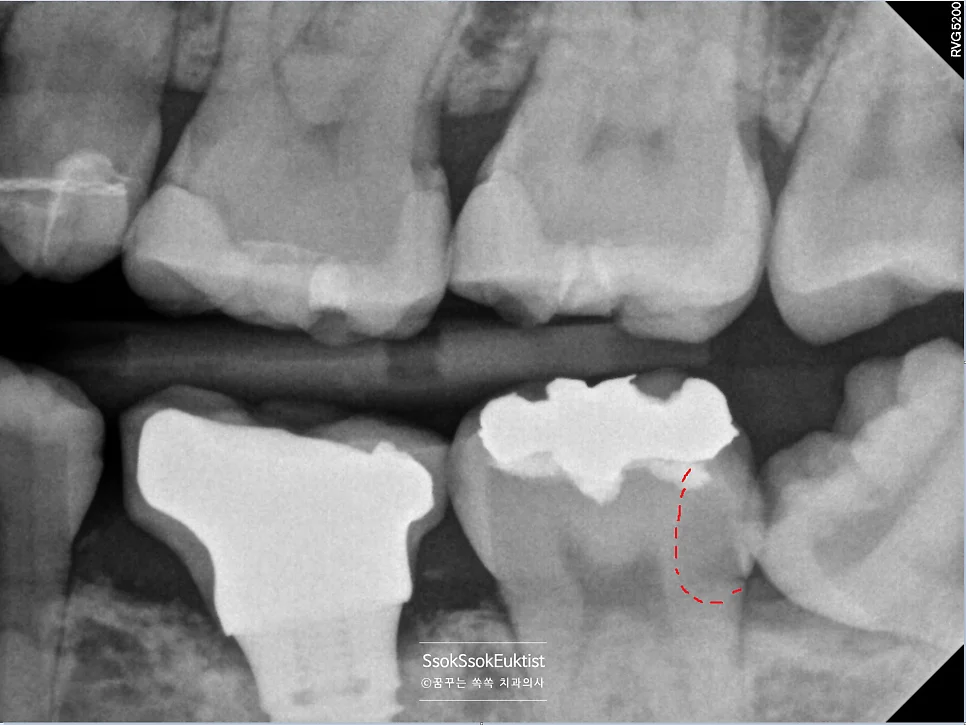

교익 방사선 사랑니 인접 충치 빨간 표시

교익 방사선(Bitewing X-ray) 사진 — 빨간색 표시 부분이 사랑니로 인해 생긴 충치

왼쪽 아래 사랑니를 촬영한 교익 방사선(Bitewing X-ray) 사진을 보면, 빨간색으로 표기한 부분이 충치인데요! 사랑니가 없었다면 절대 생기지 않을 충치입니다ㅜ

제2대구치 신경치료 완료 방사선

신경치료 완료 방사선 — 신경관이 가득 채워진 모습 (화살표: 레진으로 채워진 충치 부위)

치아의 신경관이 가득 채워진 것 같으면 잘 된 신경치료입니다^^ 한편, 크게 있던 충치도 예쁘게 레진으로 채워졌네요(사진상에서 화살표로 표시된 하얀 부분).

보통 신경치료의 경우 서울쏙쏙치과에서는 2번 정도에 마무리가 되지만, 이 치아의 경우 3번의 내원에 치료가 마무리되었습니다.